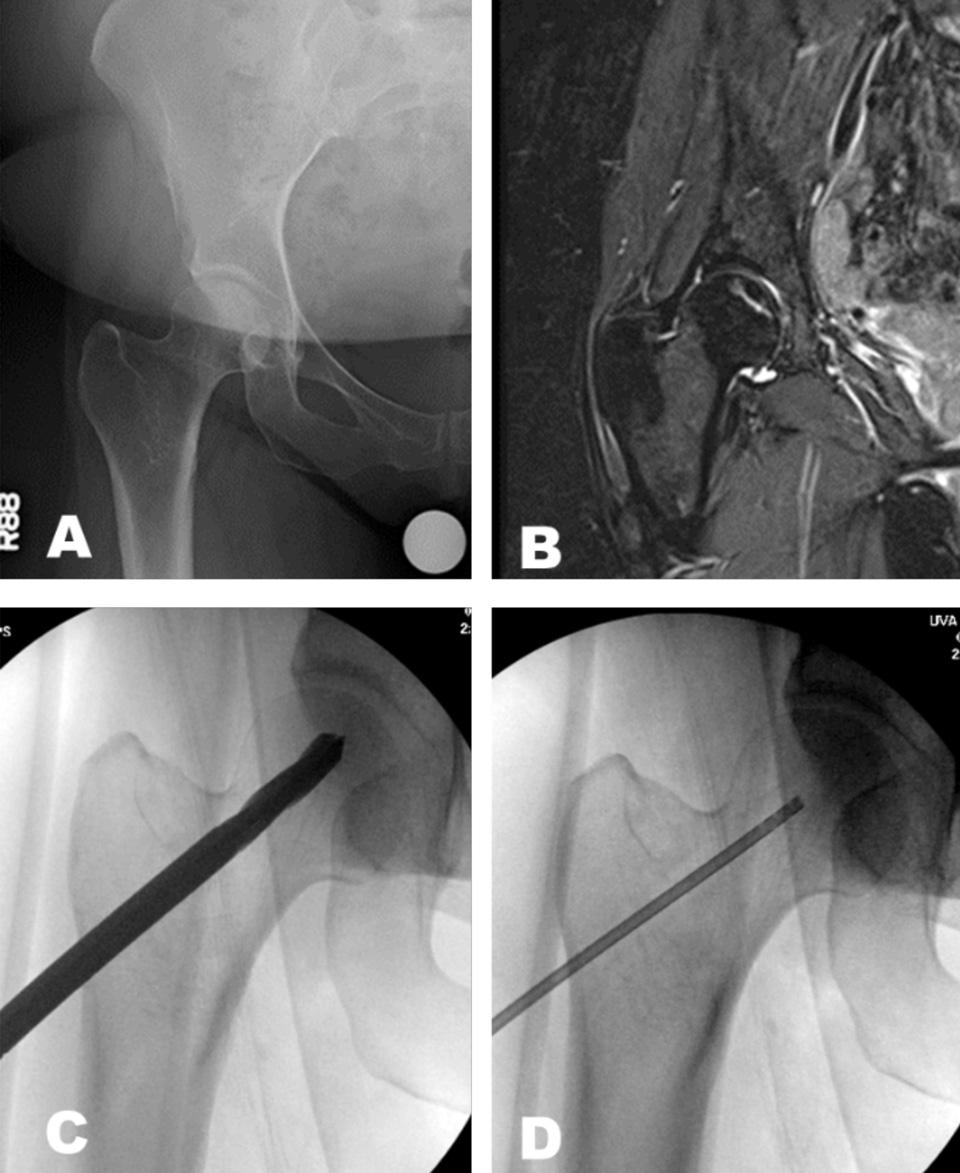

Imaging of the hip showing the femoral head and hip socket.

“We start with a precise imaging study – most likely an MRI,” Cui says. “Once we determine the location and size of the bone lesion, that dictates the treatment plan. If the assessment of the dead bone, the volume, and the location is not accurate, then the treatment will not be effective.”

Cui is one of the few orthopedic specialists in the country to offer an innovative and promising intervention for pre-collapse ONFH: core decompression (CD) with stem cell therapy. Core decompression involves drilling one or more tracts in the femoral head to restore blood flow and relieve pressure.

Next, the surgeon injects autologous bone marrow stem cells (harvested from the pelvic bone) into the femoral head to support new bone tissue growth. These cells have been found to survive and proliferate for up to 12 weeks.